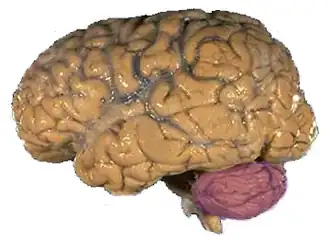

Localização do Cerebelo (em roxo) no encéfalo